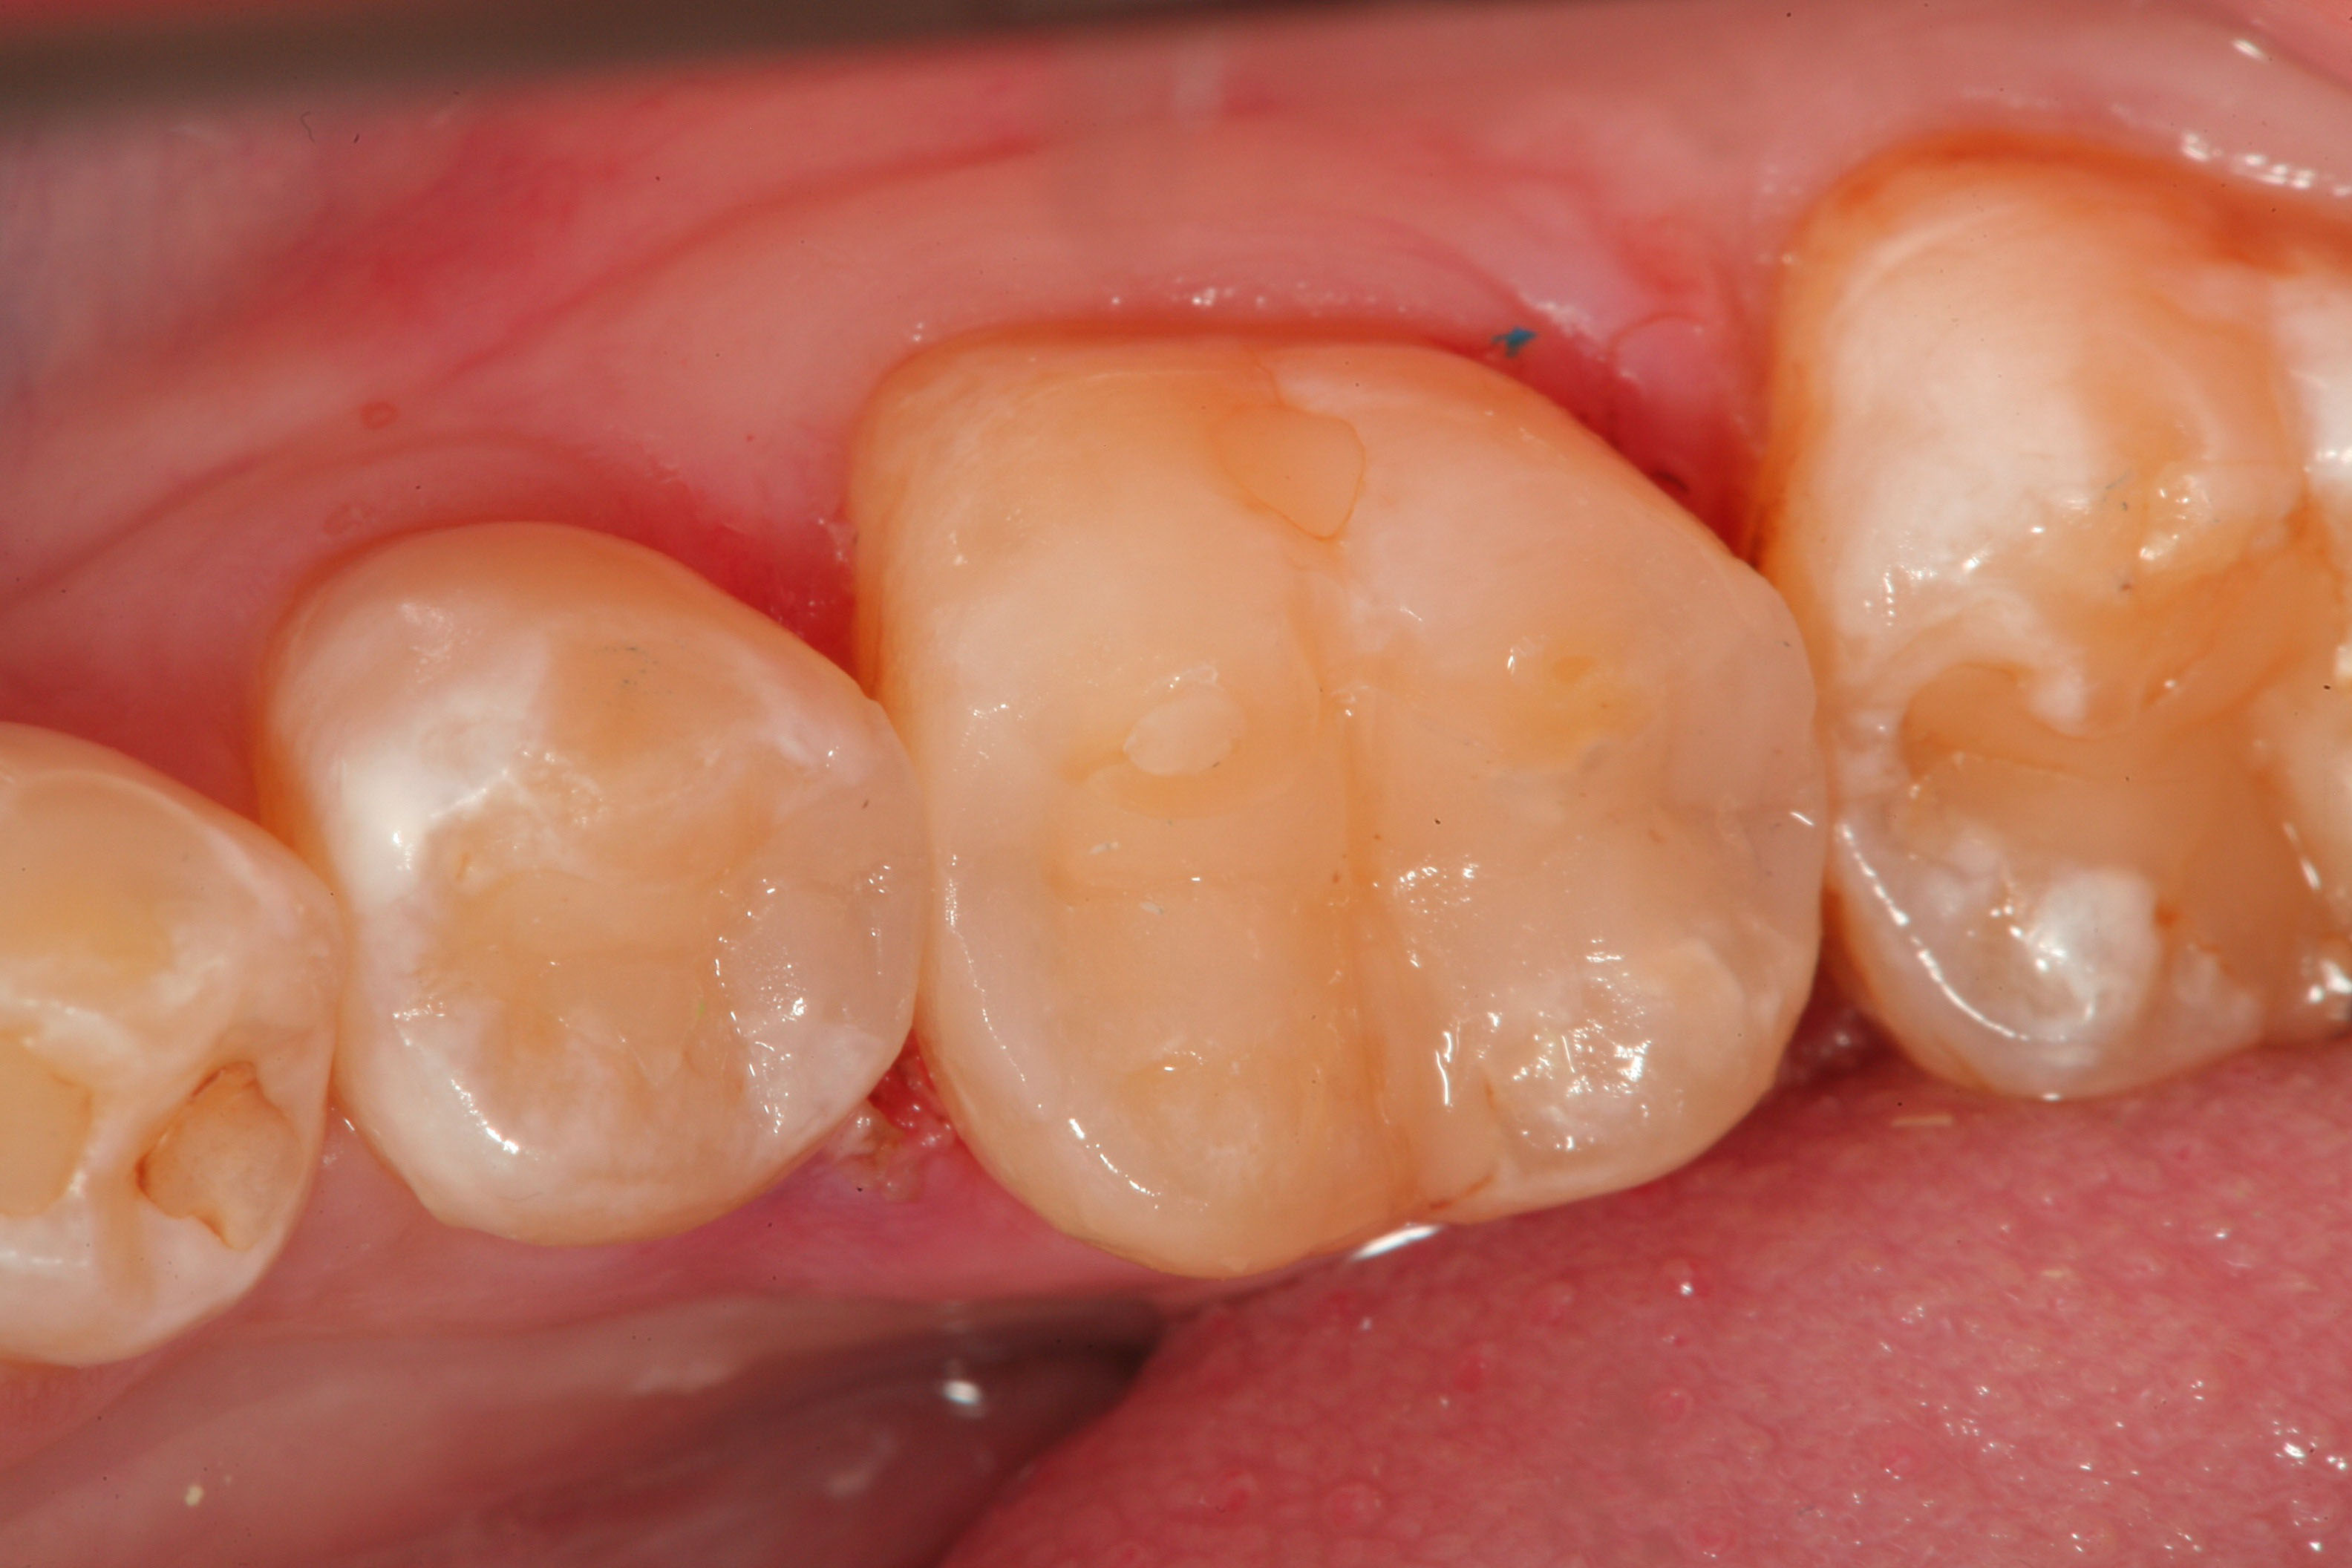

Fig 2. A Fissurotomy bur is used to remove decay found in the central groove of this mandibular premolar.

Figure 2